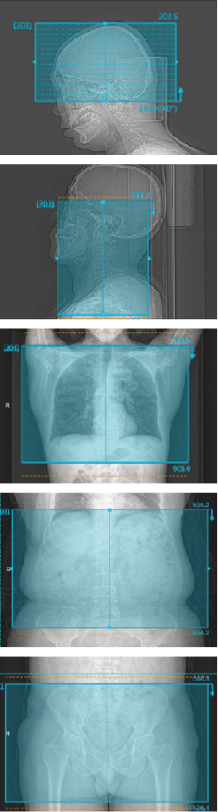

智能工作流*

自动精准识别扫描部位: 头、颈、胸、腹、盆